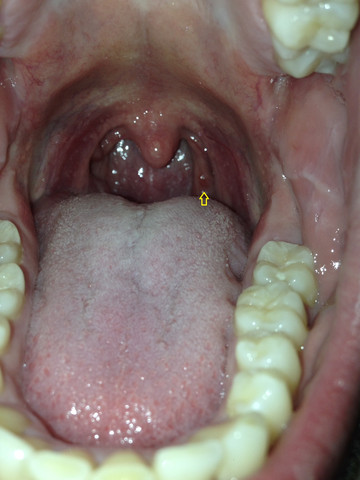

Im Allgemeinen kann davon ausgegangen werden dass bei auffälligen roten Flecken im Rachen immer ein Facharzt aufgesucht werden sollte. Herpangina oder Angina herpetica ist eine virusbedingte Gaumenmandelentzündung. Bläschen im Rachen richtig erkennen Wenn Sie den Mund weit öffnen und eine Lichtquelle zu Hilfe nehmen zum Beispiel die Taschenlampenfunktion Ihres Handys können Sie Bläschen im Rachen oft selber erkennen.

Ihr äußeres Erscheinungsbild einschließlich der Farbe hilft deinem Arzt die zugrunde liegende Ursache zu erkennen. Die Mandeln sind nur schwach gerötet und leicht geschwollen anfangs ist die Rachen- und Gaumenschleimhaut von weißlich-gelben Bläschen übersät.